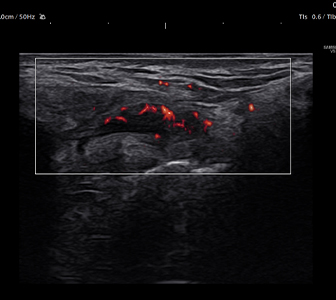

微小血流や低流速血流を可視化。

※Segmentation™機能は、描出した画像から、

筋・血流・神経・骨を⾃動的に区分けします。